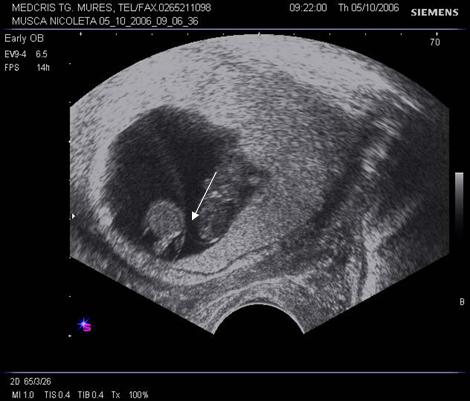

Fig nr 36 Sarcina gemelara biamniotica, 6 sapt, cu 2

saci amniotici si 2 embrioni (cu sageata )